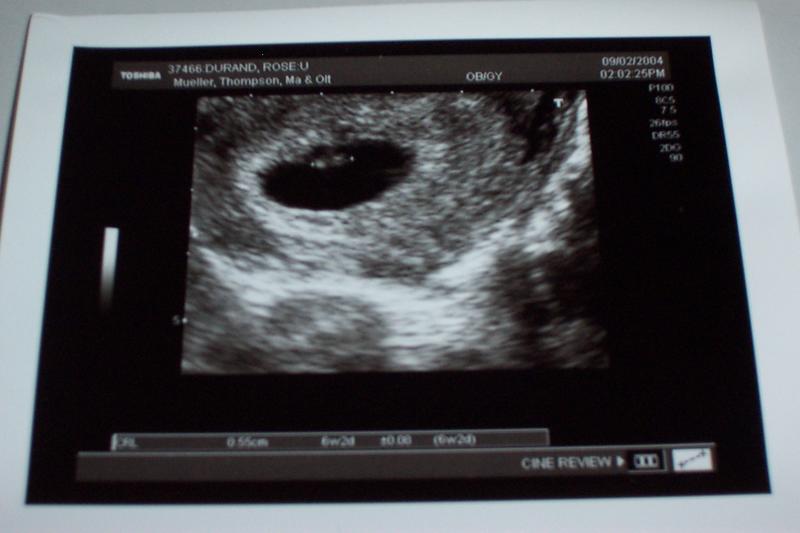

First Ultrasound